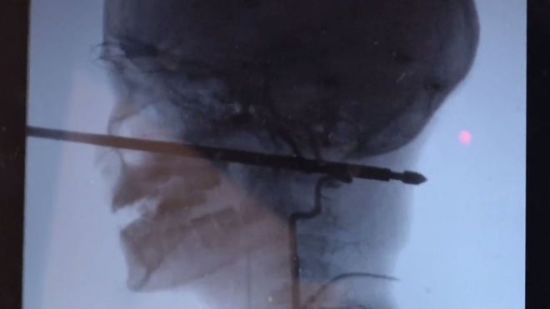

Хирургическое чудо. В американском штате Канзас врачи спасли 10-летнего мальчика, которому шампур для мяса пробил голову. Ксавье играл в доме на дереве, как вдруг на него напали осы и он упал прямо на рожон. glavnoe.ua »

10-летний американец Ксавьер Каннингем играл в домике на дереве. На него напал рой ос, вследствие чего парень упал с высоты 1 м и напоролся головой на 30-сантиметровый шампур. Инцидент произошел в штате Миссури. gazeta.ua »

В американском Миссури 10-летний Ксавьер Каннингем выжил после того, как металлический шампур проткнул его голову. Об этом сообщает Daily Mail. Мальчик решил поиграть в домике на дереве, но там на него напал рой ос. inforesist.org »

Чудом металлический стержень не повредил школьнику глаз, мозг и крупные сосуды. ru.tsn.ua »